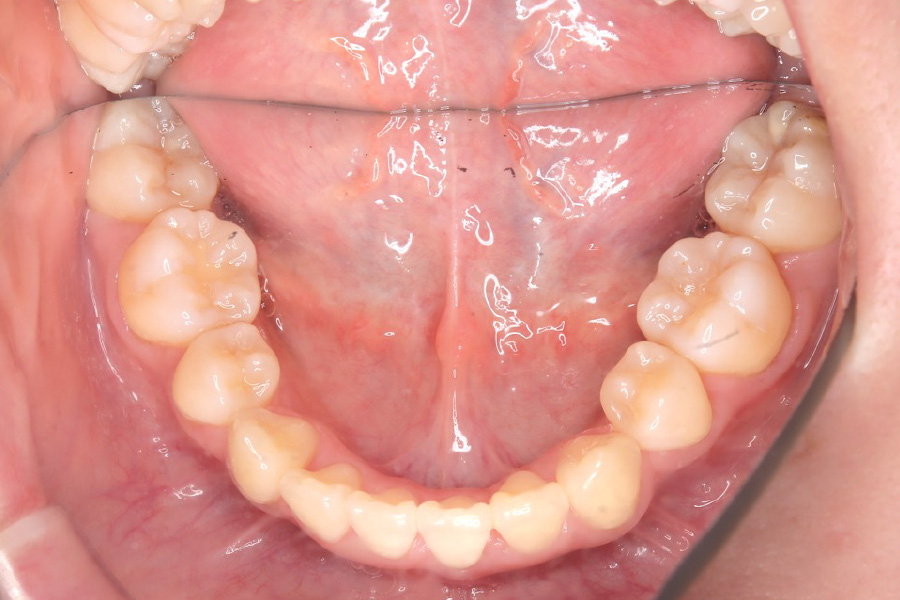

治療後

主訴 全体のガタつきが気になる

期間 2年

費用 220,000円〜660,000円

治療内容 インザライン矯正

小臼歯抜歯

治療に伴うリスク 矯正終了後は、リテーナーを指示通りに使用し、歯の後戻りを防ぐ必要があります。